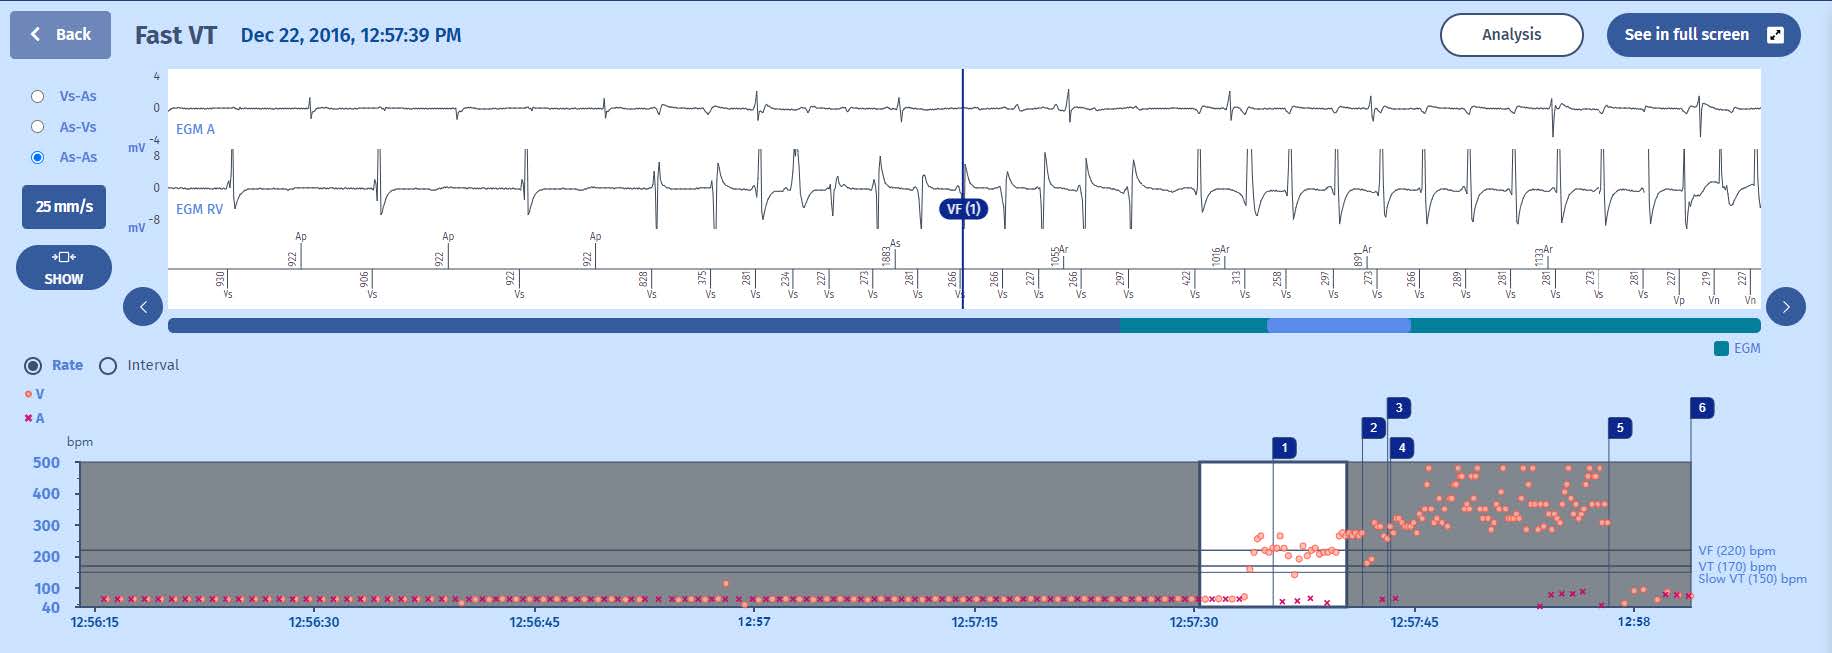

This example explains the sequence of therapies in the FVT/VF zone.

1 The tachycardia is immediately detected in the VF zone after 8 tachycardia cycles. We can see that the tachycardia is not stable at the outset

2 A persistence of 16 cycles is therefore triggered at the end of which

3 the first therapy in the FVT zone is initiated since the tachycardia is still in the VF zone at the end of the persistence with a stable rhythm: the therapy delivered is an 8-cycle burst

4 This degrades the tachycardia into a ventricular fibrillation, first observed in the VT zone (VTLC marker) since the first two cycles after the ATP are longer and diagnosed as VF in the next cycle (VF marker), hence a new persistence of 16 cycles is triggered.

5 The second line of therapy consists in shocks, hence the charge of the capacitors.

6 The VF continued throughout the charge, the device was able to confirm the charge cycle-to-cycle, and at the end of the charge, a 195 ms cycle confirms that the VF continues, and thus a shock is delivered (37.3 J).

7 The first signal after the shock is the opening of the detection chains (for the implant, the coupling interval of this cycle is 164 ms: the post-shock interval is 1164ms that quals the one-second blanking period plus 164 ms), the ensuing 6 cycles are slow

which terminate the episode.